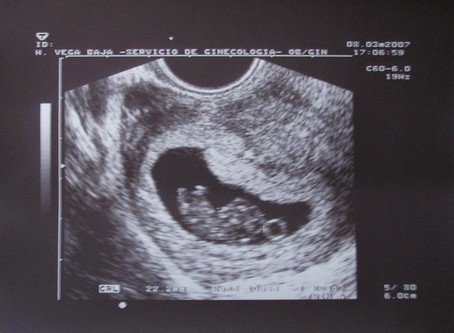

újra gratu és duplán